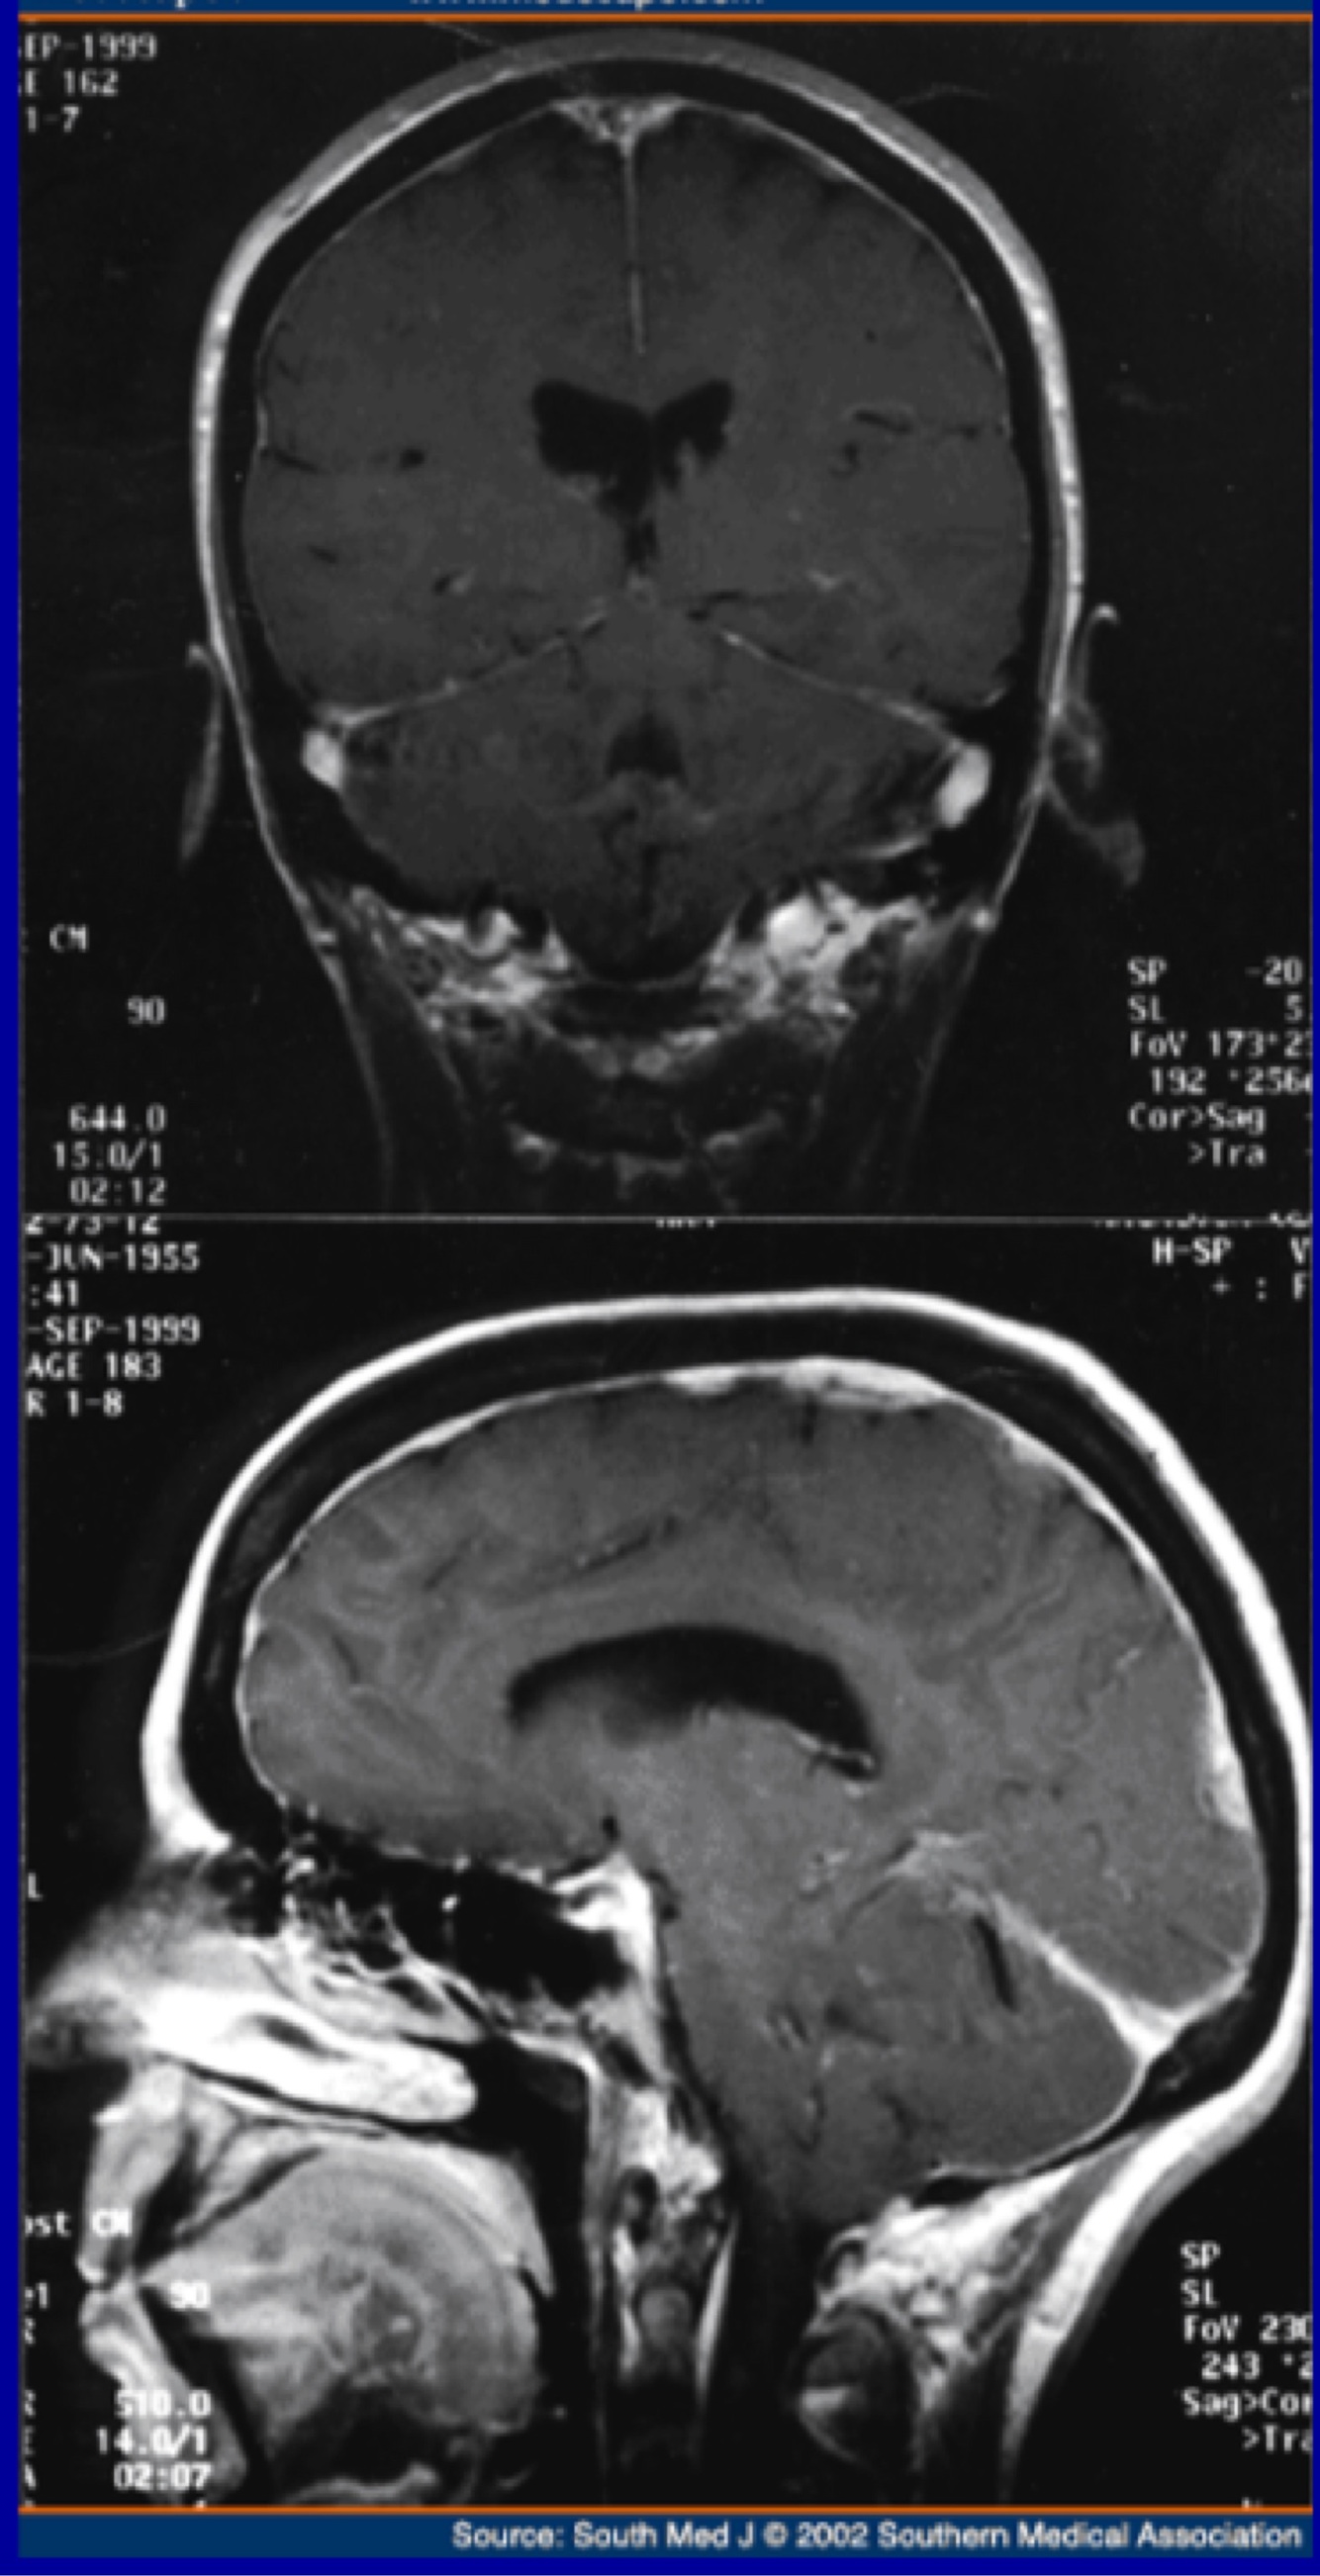

Raised CSF pressure (hydrocephalus, intracranial hypertension)

What is the investigation of intracranial hypotension

MRI brain and spine to show characteristic features